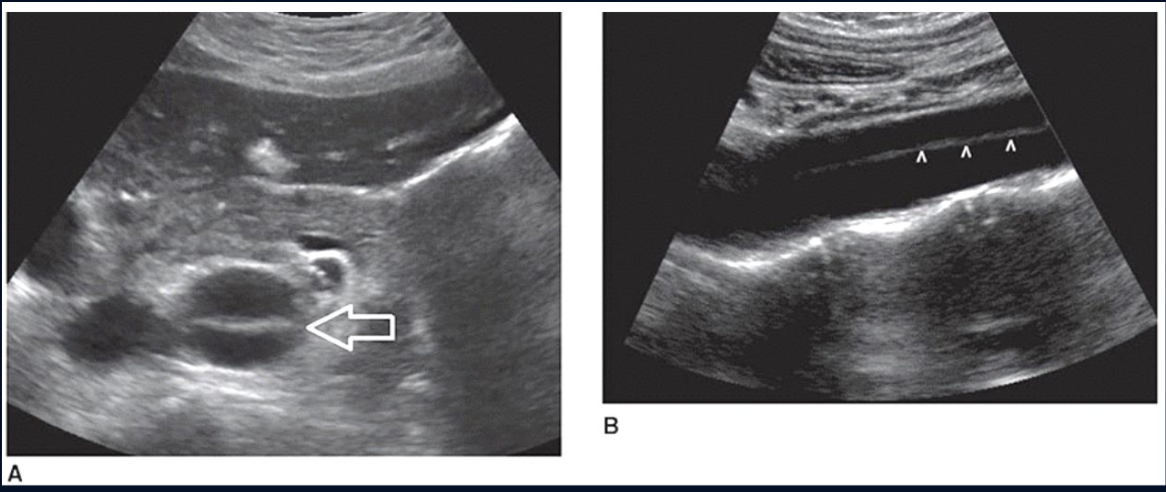

what is the arrow pointing to

Normal IVC (as it can be compressed)

Pathology?

DVT in the Common femoral vein